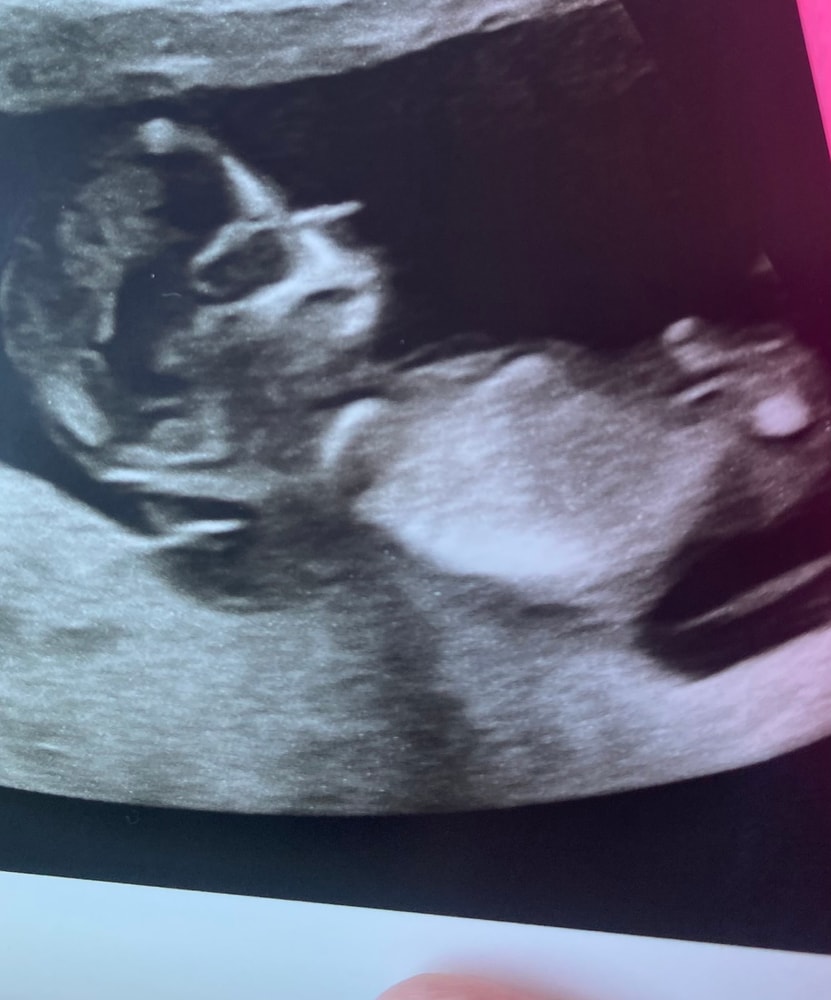

Kroshka, Изображение

31.10.2025

Жасмин К, бугорка полового особо не видно, и пуповинка закрывает. Вам если надо быстро точно и срочно, вы сдайте кровь на определение пола ребёнка, он вроде 3-5 дней готовится